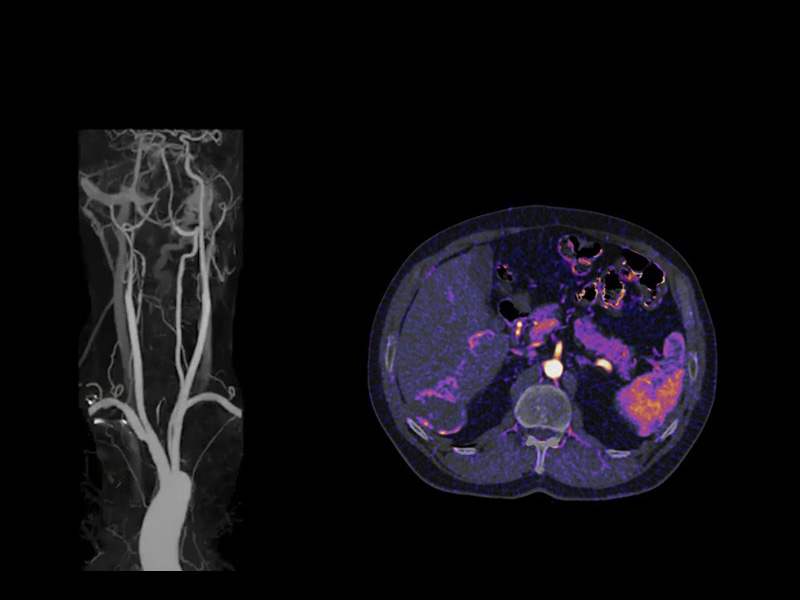

Автоматическое вычитание кости и / или картирование йода. URE SURE Subtraction ™

При CTA-обследованиях SURE Subtraction обладает способностью удалять кости, кальций и стенты из наборов данных, что позволяет врачам беспрепятственно просматривать артерии.

Кроме того, SURE Subtraction может создавать карты йода для оценки распределения контрастных веществ в организме для визуализации локальной перфузии.

SURE Subtraction имеет интегрированную по протоколу автоматизацию на каждом этапе, чтобы дать даже начинающему оператору навыки, позволяющие блестяще работать с первого раза - каждый раз.

До вычитания деформируемая регистрация Canon Medical Systems позволяет сопоставлять пиксели между данными предварительного контраста и контраста для точного цифрового вычитания и йодного картирования, экономя время и улучшая диагностическую точность.